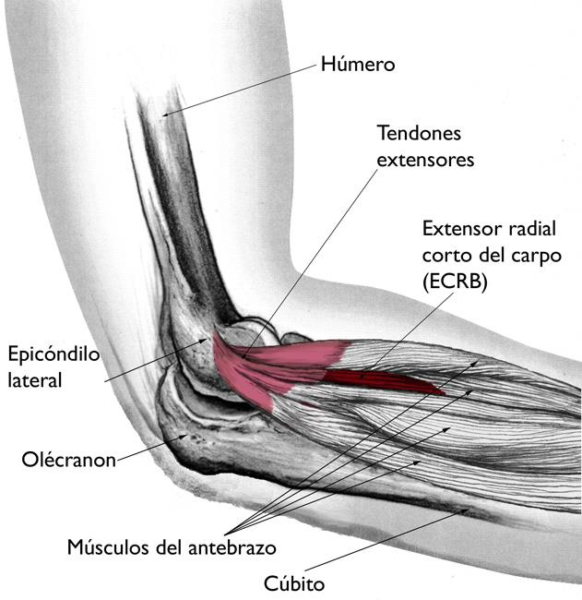

Codo de tenista en tenis, o epicondilitis lateral, es una tendinopatía de los tendones extensores del antebrazo que se insertan en la parte externa del codo. En tenis, se relaciona con gestos repetidos como el revés, sobre todo a una mano, y con impactos descentrados que obligan al antebrazo a “sujetar” vibraciones extra. El resultado es dolor y sensibilidad en la zona externa del codo al golpear, agarrar o levantar peso.

La zona dolorosa típica está en el lateral externo del codo, donde se insertan los tendones extensores de la muñeca y los dedos. Cada vez que sujetas la raqueta, ajustas el ángulo de la muñeca o estabilizas el impacto, esa musculatura trabaja. Si el gesto técnico no acompaña, el codo acaba haciendo de “amortiguador” de muchas fuerzas que podrían repartirse mejor.

Tomado y modificado de The Body Almanac. (c) American Academy of Orthopaedic Surgeons, 2003.